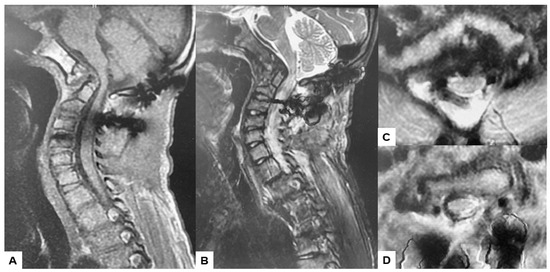

2.3. Preoperative Imaging